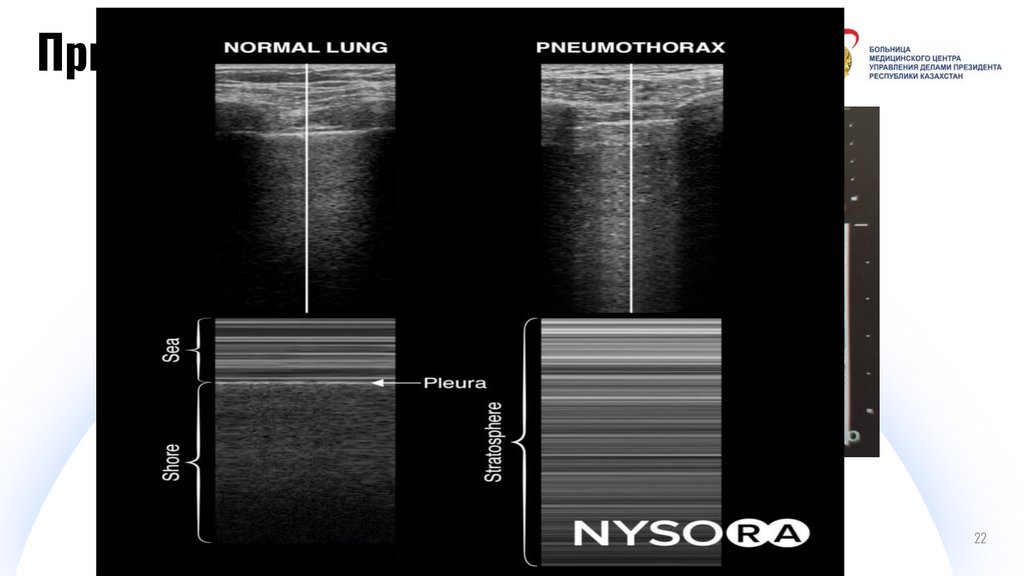

Признаки пневмоторакса

И

Отсутствие скольжения

плевры

Digital IT pitch-deck PowerPoint bundle

Баркод

22